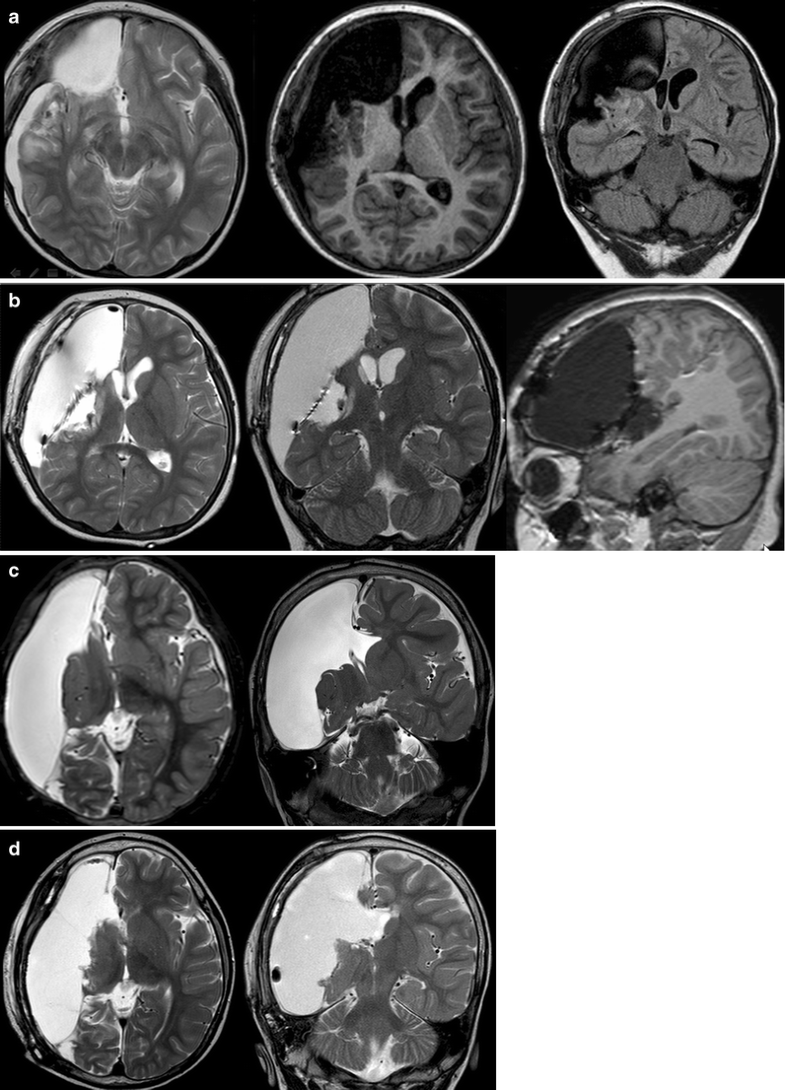

(PDF) Stereotactic placement of depth electrodes in medically Depth Electrodes Epilepsy Surgery The two types of intracranial electrodes most commonly used for preoperative evaluation are subdural and depth electrodes. The stereotactic electroencephalography (seeg) lead implantation is an invasive method of monitoring and localizing seizure foci in. Typical targets for depth electrode insertions are the calcarine and pericalcarine. Intracranial electroencephalographic monitoring with subdural and/or depth electrodes is widely used for the surgical localization. Depth Electrodes Epilepsy Surgery.

(PDF) MRIguided stereotactic implantation of depth electrodes in Depth Electrodes Epilepsy Surgery Typical targets for depth electrode insertions are the calcarine and pericalcarine. This article reviews the usefulness, methods, and limitations of invasive. The two types of intracranial electrodes most commonly used for preoperative evaluation are subdural and depth electrodes. Intracranial electroencephalographic monitoring with subdural and/or depth electrodes is widely used for the surgical localization of epileptic. The stereotactic electroencephalography (seeg) lead. Depth Electrodes Epilepsy Surgery.

CT image of depth electrodes implantation scheme. Download Scientific Depth Electrodes Epilepsy Surgery The stereotactic electroencephalography (seeg) lead implantation is an invasive method of monitoring and localizing seizure foci in. Typical targets for depth electrode insertions are the calcarine and pericalcarine. The two types of intracranial electrodes most commonly used for preoperative evaluation are subdural and depth electrodes. Intracranial electroencephalographic monitoring with subdural and/or depth electrodes is widely used for the surgical localization. Depth Electrodes Epilepsy Surgery.

Stereotactic Placement of Temporal Depth Electrodes Neupsy Key Depth Electrodes Epilepsy Surgery The stereotactic electroencephalography (seeg) lead implantation is an invasive method of monitoring and localizing seizure foci in. Typical targets for depth electrode insertions are the calcarine and pericalcarine. This article reviews the usefulness, methods, and limitations of invasive. Intracranial electroencephalographic monitoring with subdural and/or depth electrodes is widely used for the surgical localization of epileptic. The two types of intracranial. Depth Electrodes Epilepsy Surgery.

(PDF) Hippocampal Depth Electrodes in Epilepsy Surgery Diagnostic or Depth Electrodes Epilepsy Surgery This article reviews the usefulness, methods, and limitations of invasive. The two types of intracranial electrodes most commonly used for preoperative evaluation are subdural and depth electrodes. Typical targets for depth electrode insertions are the calcarine and pericalcarine. Intracranial electroencephalographic monitoring with subdural and/or depth electrodes is widely used for the surgical localization of epileptic. The stereotactic electroencephalography (seeg) lead. Depth Electrodes Epilepsy Surgery.